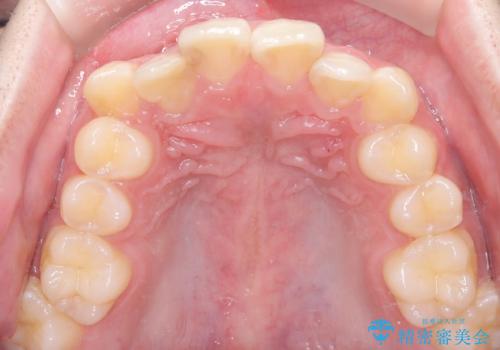

- 主訴:右上の前歯が何しなくても痛い

右上2番の歯に自発痛を認め、症状や歯髄診・レントゲン像から不可逆性歯髄炎と診断し、精密根管治療から歯冠補綴まで行うこととなりました。

初診時に歯髄診断を行い、不可逆性歯髄炎と診断し抜髄から補綴修復までの流れを説明し、精密根管治療、ファイバ-コア築造、オールセラミッククラウン(St)修復を行うこととしました。